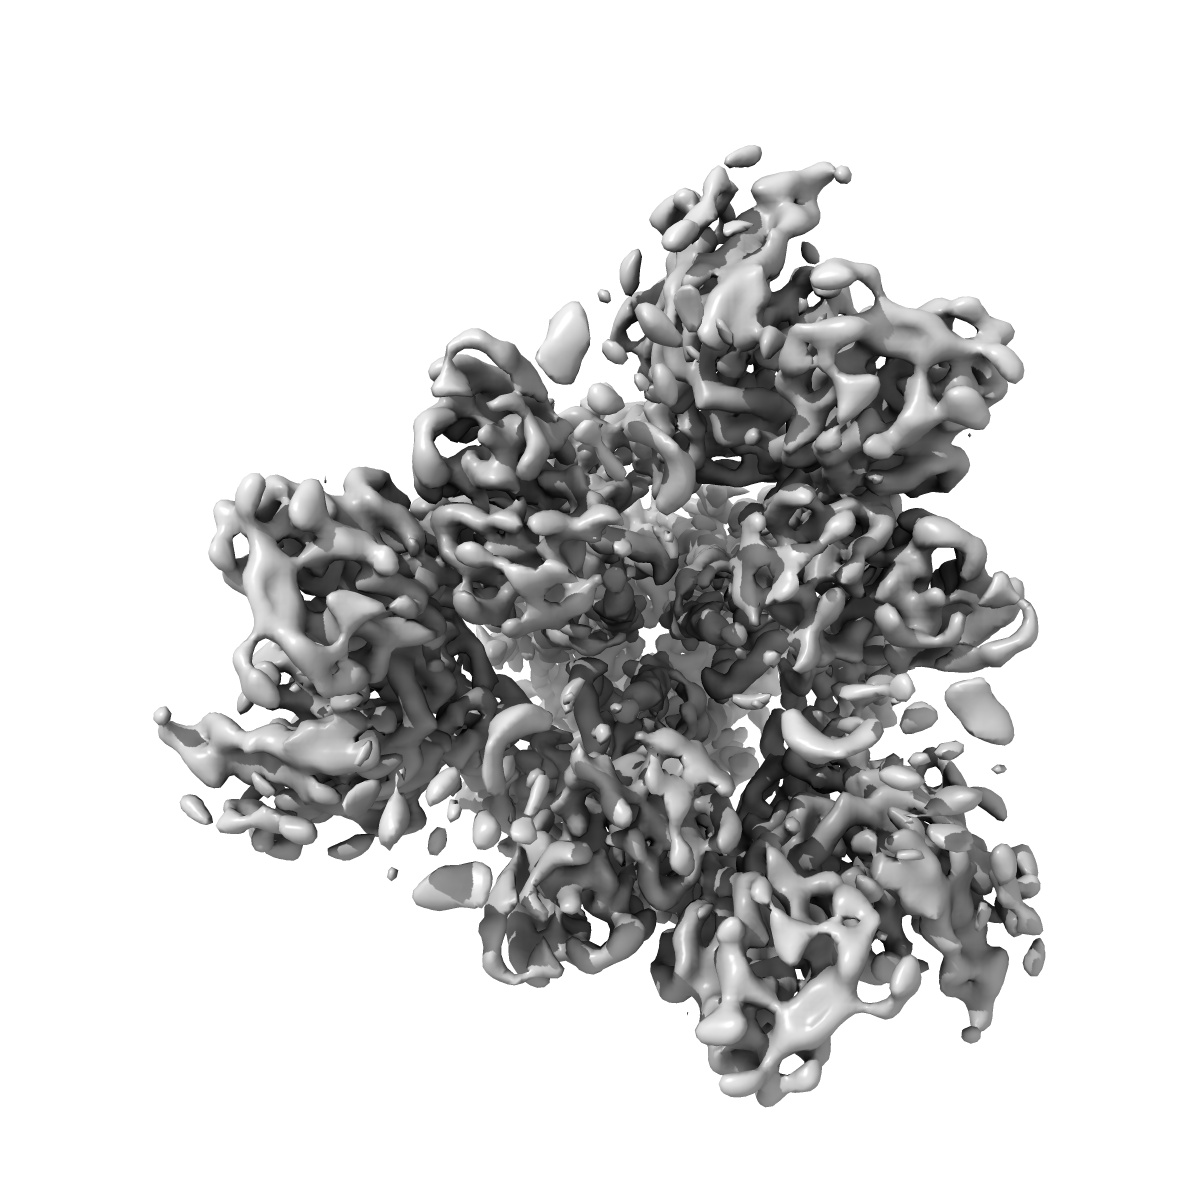

SARS-CoV-2 spike in complex with the S304 neutralizing antibody Fab fragment

Single-particle4.3 Å

Sample: SARS-CoV-2 spike in complex with the S304 neutralizing antibody Fab fragment